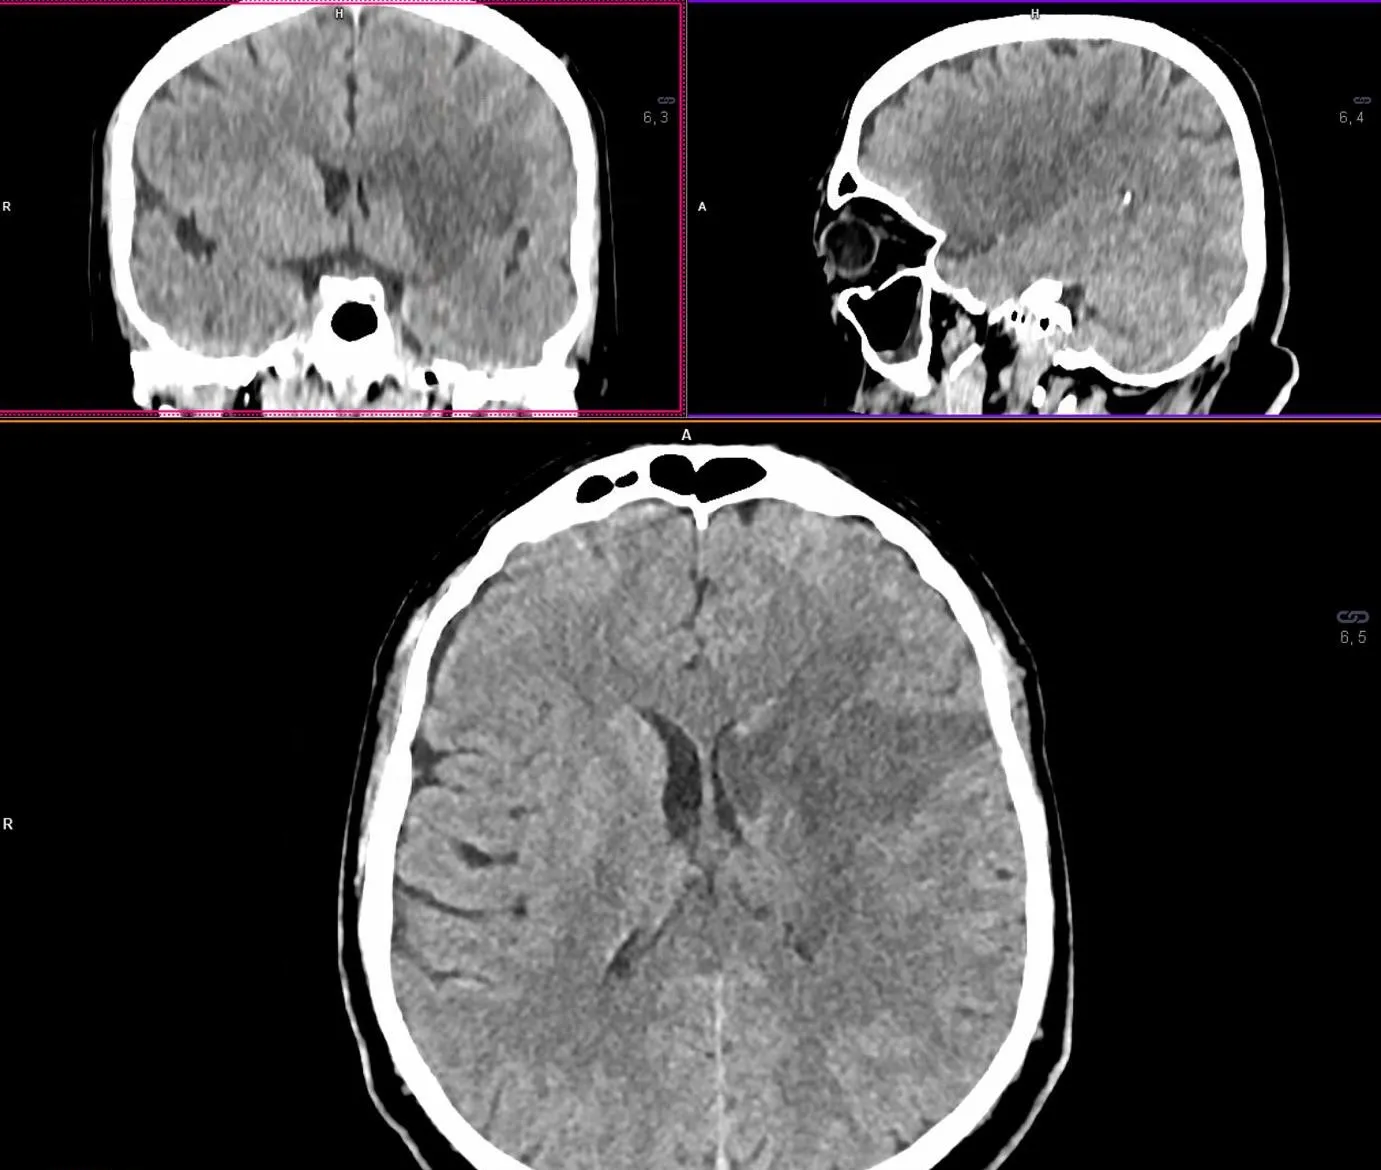

Рисунок 3. МСКТ-перфузійні зображення пацієнта Д.

Представлені карти МСКТ-перфузійних зображень демонструють зони дуже низької перфузії при CBV (a) та CBF (b), що відповідають ядру інфаркту (біла стрілка), та велику зону, що відповідаї пенумбрі (зелений овал) при TMax-map (c).

Відповідно до результатів нейровізуалізації та візуалізації церебральних артерій у пацієнта Д. був діагностований ішемічний інсульт, що обумовлений оклюзією великої мозкової артерії (лівої внутрішньої сонної артерії [ВСА] та лівої середньої мозкової артерії [СМА]). Згідно з результатами автоматичного обчислення, на момент дослідження об’єм ядра інфаркту у пацієнта Д. склав 24,6 см3, а об’єм зони пенумбри – 47,9 см3. Отже, об’єм зони пенумбри становив 194,7% об’єму ядра (співвідношення пенумбри та інфаркта майже 2:1). Зважаючи на це, ситуація була обговорена з лікарем-нейрохірургом С. В. Конотопчиком і о 14:45 пацієнт бригадою НМД «Оберіг» був доправлений у ДУ «НПЦ Ендоваскулярної нейрорентгенохірургії НАМН України» та спрямований одразу до операційної.